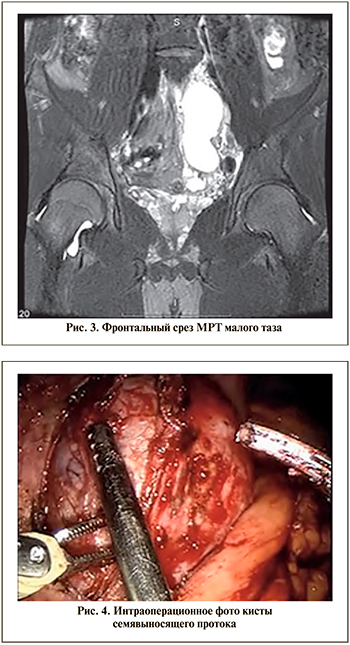

С целью дообследования пациенту выполнена МРТ органов малого таза, по данным которой обнаружены киста проксимальных отделов левого семявыносящего протока, расширение проксимальных отделов правого семявыносящего протока, увеличение в размерах и дилатация левого семенного пузырька, расширение левого семявыбрасывающего протока (рис. 2, 3).

С учетом возраста пациента, вышеуказанных симптомов решено выполнить оперативное вмешательство робот-ассистированным способом: удаление кисты левого семенного пузырька.

В январе 2020 г. под эндотрахеальным наркозом выполнено оперативное лечение. При ревизии после мобилизации сигмовидной кишки и рассечения тазовой брюшины обнаружено образование размером 10,0х6,0 см продолговатой неправильной формы. Образование снизу интимно прилежало к подвздошным сосудам, верхний сегмент его заканчивался на уровне промонториума, нижний – на уровне левой боковой стенки мочевого пузыря. При помощи би- и монополярной коагуляций образование выделено из окружающей ткани, последнее вскрыто, эвакуировано около 80 мл бурой жидкости. Левый семенной катаник лигирован при помощи клипс «hem-o-lock» и пересечен. После окончательной мобилизации образования последнее удалено через троакарный доступ (рис. 4).

Результат гистологического заключения: киста левого семявыносящего протока. У пациента в послеоперационном периоде не отмечено осложнений.